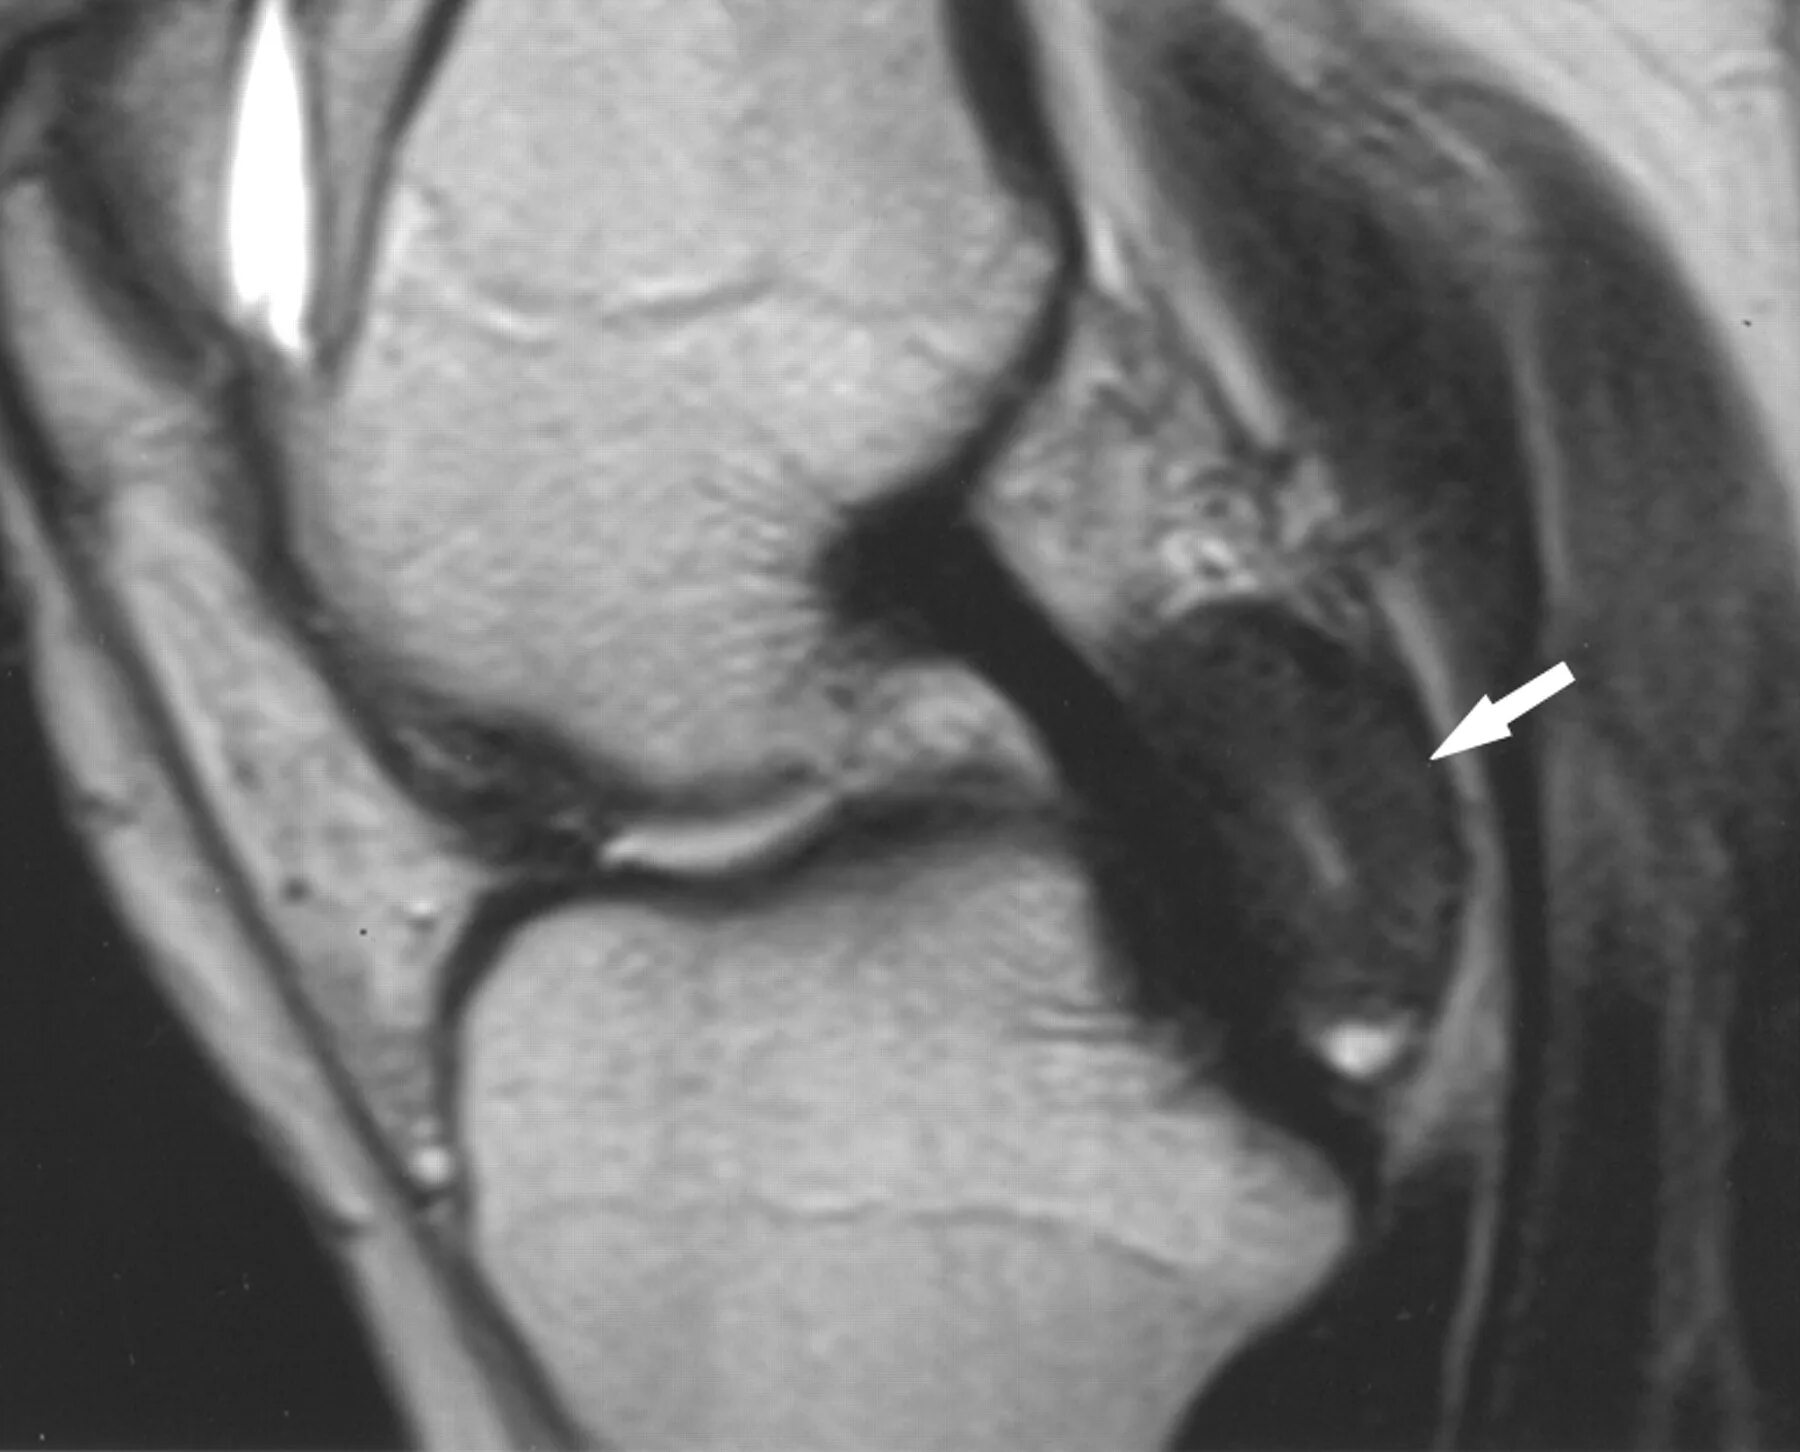

Синовиомы